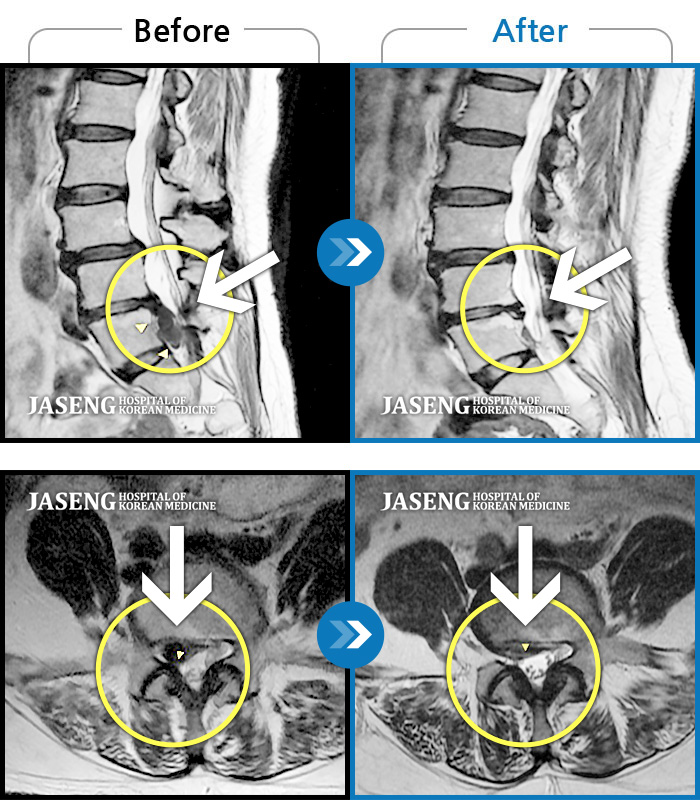

허리디스크

해운대 · 이상건 원장

허리디스크로 인한 요통

촬영시기

2018.04.21 ~ 2018.11.10